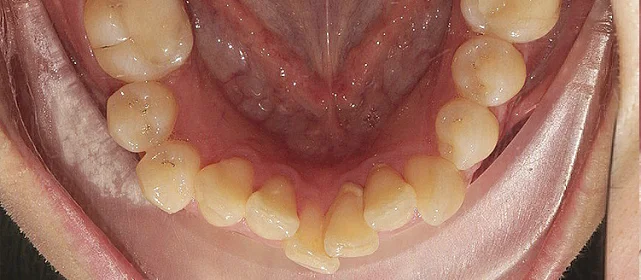

Обе челюсти сужены — зубам не хватало места, они стояли скученно на верхней и нижней челюсти. Нарушена кривая смыкания — жевательные зубы были на разной высоте.

Проблема: Пациентка живёт за рубежом и обратилась с жалобами на неровные зубы. При осмотре обнаружили сужение обеих челюстей, скученность на верхней и нижней, а также деформацию кривой смыкания — жевательные зубы стояли на разной высоте, из-за чего нагрузка при еде распределялась неравномерно. Дополнительная сложность — пациентка не могла приезжать на визиты часто.

Сложный случай: скученность на обеих челюстях плюс деформация кривой Шпее — жевательные зубы на разной высоте. Дополнительный вызов — пациентка живёт за рубежом, визиты реже, контроль сложнее. Три дозаказа — много, но каждый был обоснован: основной набор расширил дуги и убрал основную скученность, дозаказы последовательно довели смыкание до нормы. 82 капы за 30 месяцев — результат получен.